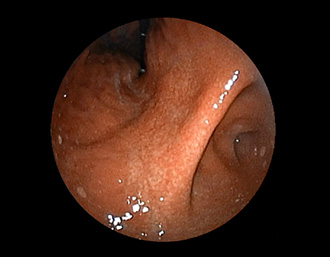

症例3:十二指腸潰瘍(53才男性)

1年前からの慢性胃痛を主訴に当院受診。十二指腸球部前壁に深くて大きな潰瘍(Stage A1)があり、潰瘍底は厚い白苔に覆われ、一部白苔のはみ出しを認める。潰瘍周囲粘膜は浮腫を伴っている。ボノプラザンフマル酸塩投薬で治療開始しました。

(通常画像)

(FICE画像)

(インジゴカルミン散布画像)

(FICE+インジゴカルミン散布画像)